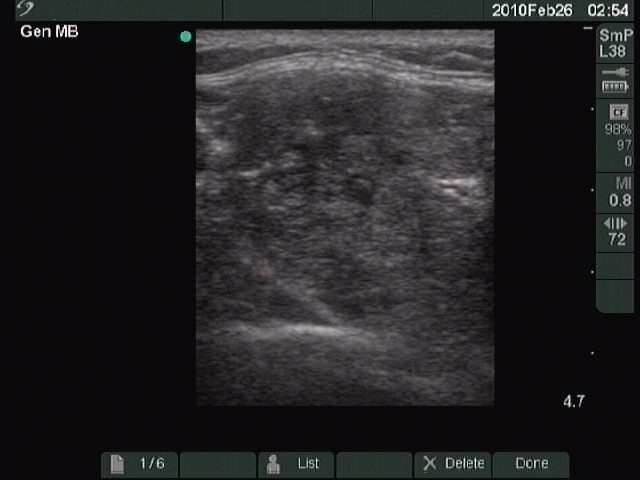

Benign nodular hyperplasia - Case 27. |

Clinical presentation: a 48-year-old woman was referred for an evaluation of a 'lump in the throat' feeling.

Palpation: both lobes of the thyroid were enlarged, but caused no complaints to the patient.

Functional state: euthyroidism.

Ultrasonography: multinodular goiter.

Cytological report: benign colloid goiter.

Suggestion: follow-up examination.